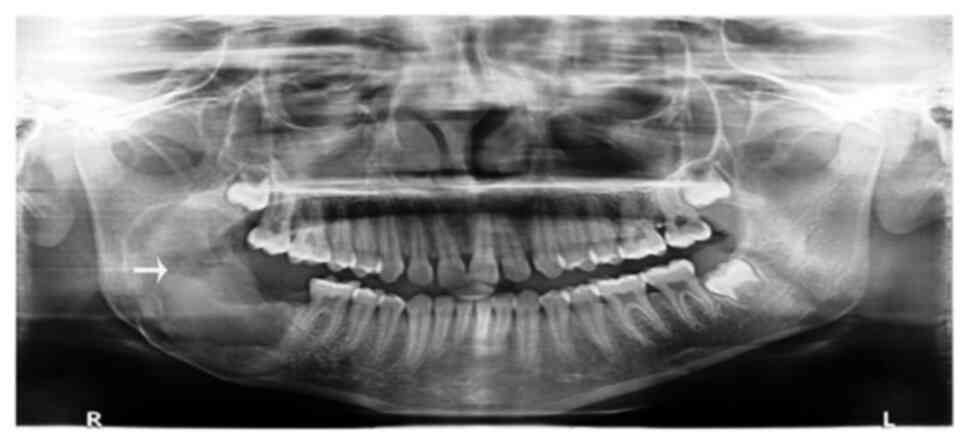

Based on a comprehensive clinical and radiographic assessment, a tentative diagnosis of odontoameloblastoma, calcifying cystic odontogenic tumor, complex or compound odontoma, ameloblastic fibroma (AF), or ameloblastic fibro-dentinoma (AFD) was made. Following a scrupulous pre-surgical evaluation, the procedure was performed under general anesthesia, with an intraoral approach selected for the enucleation of the lesion along with the third molar. The extraction of the right second mandibular molar was performed due to root resorption. The curettage of the bony walls was subsequently performed, as illustrated in Fig. 2. Bone smoothing was accomplished, and the excision site was securely sutured with 3-0 vicryl sutures. Intermaxillary fixation was performed to immobilize the mandible and prevent any pathological fracture of the mandibular body.

Figure 2

Surgical enucleation of the lesion with an impacted third molar.